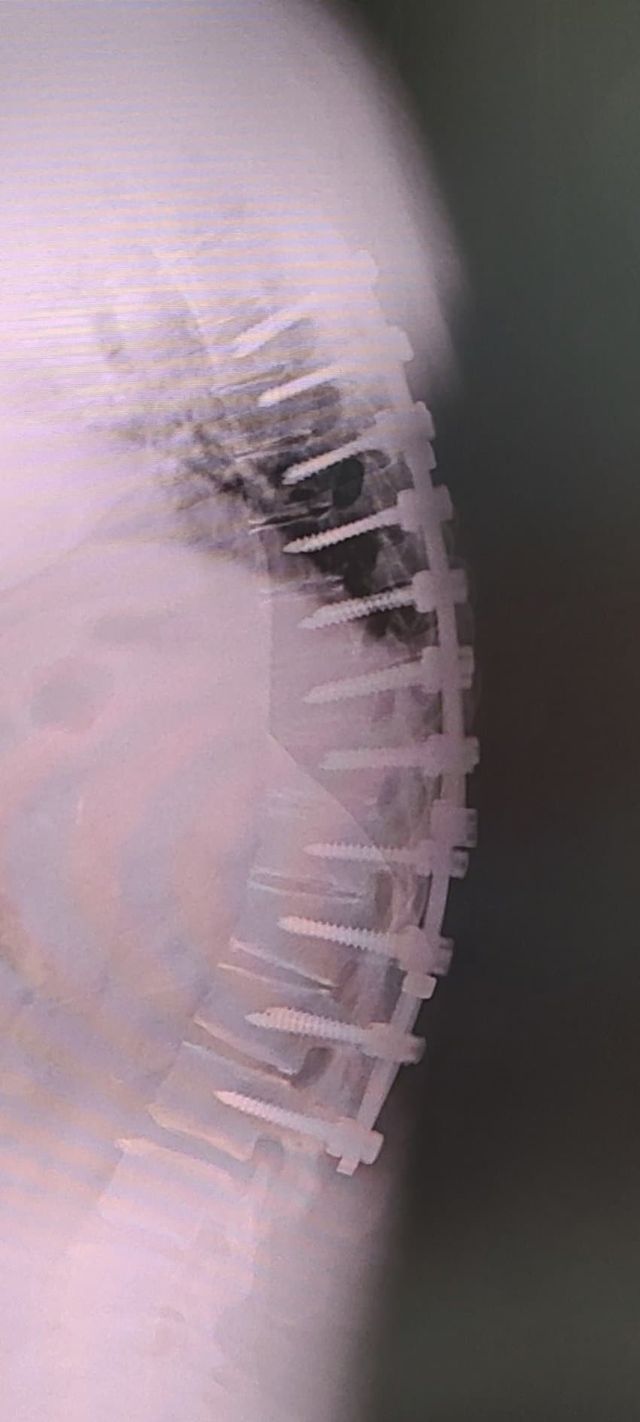

디씨)나 12사에서 죽을뻔하고 척추에 심 21개 박은 사람이다!?

나도 12사때 훈련병시절 완전 군장하고 쓰러지고

척추 무너지고 희귀병 진단받아서

12사 내 의무사단에서 핵고통 받다가 죽다살아난 사람이다